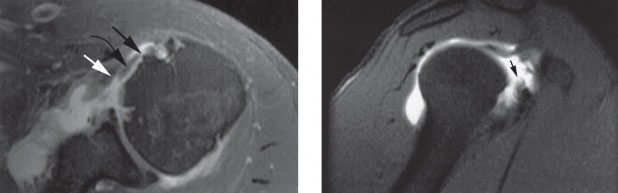

Figure 2–8_Reproduced with permission from Stadnick ME. _Partial Rotator Cuff Tears. MRI Web Clinic. 2007 (Apr).

The correct answer is (A). These are best diagnosed on an MRI as seen in the imaging provided; addition of intra-articular contrast can further improve this study. Answer B, full-thickness rotator cuff tear, is incorrect as the bursal side of the tendon can be seen to be in continuity. Answer C, a SLAP lesion, will be visualized as a labral tear on a coronal MRI and will be found at the biceps root. Answer D, an ALPSA lesion, will be most clearly seen on an axial MRI. It is a variant of a Bankart lesion where the labrum is displaced medially and inferiorly rolling down the glenoid neck underneath the periosteum.

MRI remains the most popular imaging modality for diagnosing rotator cuff tears. Normal rotator cuff tendon appears dark on both T1 and T2 sequences. Tears may be noted as being full-thickness, articular-sided, bursal-sided, or intrasubstance. They are visualized as a disruption in the regular contour of the tendon and increased signal intensity on T2 sequences. Occasionally, an MR arthrogram may provide additional information regarding a cuff tear, although this is not routinely ordered.

Figure 2–9_From Shi LL, Mullen MG, Freehill MT, et al. Accuracy of Long Head of the Biceps Subluxation as a Predictor for Subscapularis Tears. _Arthroscopy 2015;32(4):615–619.

The correct answer is (A). Medial subluxation of the biceps tendon as seen in this MRI is commonly associated with a tear of the subscapularis tendon which attaches to the lesser tuberosity. This patient’s pain may in part be attributable to the subscapular tear and this should be evaluated for during physical examination. Supraspinatus tears (Answer B) cannot be easily visualized on axial views and are not associated with medial biceps subluxations. A labral tear and ALPSA lesion (Answers C and D) are not seen on the images provided. The question stem and MRI are not suggestive of shoulder instability (Answer E). Objectives: Did you learn...? Diagnose and treat acute rotator cuff tears?